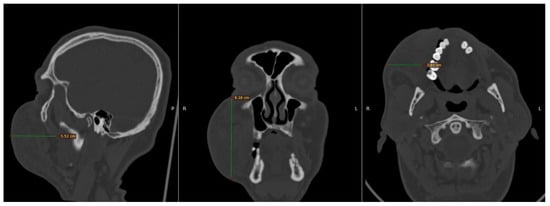

To elucidate the nature and extent of the observed pathology, the patient underwent an urgent computed tomography (CT) scan of the craniofacial region. The imaging study disclosed a substantial hyperdense lesion within the right buccal space, with dimensions measuring 3.8 cm × 8.4 cm × 5.5 cm, as depicted in Figure 1. This radiographic finding corroborated the clinical suspicion of a significant hematoma.

Figure 1.

Computed tomography (CT), which was performed in the Emergency Department. The maximum dimensions of the lesion in the right buccal area measured 3.8 × 8.4 × 5.5 cm.